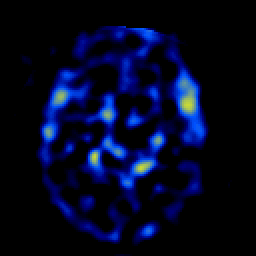

SPECT TL Study #4 -- Slice #27